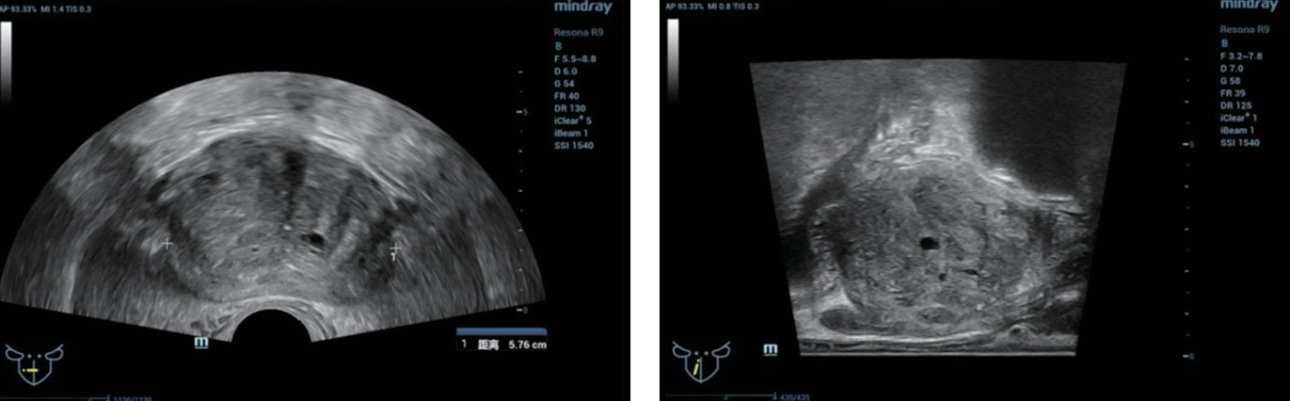

TRUS ?? (figure 1):?

- ??? ??? ???? ??? ??? ???.

- ? ??? ???? ?? ??(heterogeneous) ??? echotexture.

?? ? ?? ??: ??? ??? ???? ????? ??? ??? ? ??? ???, ??? TRUS/MRI ?? ???? ??? ?? ??? 12-point systemic needle ?? ??? ???? ?????.

Systemic ??? ?? ?? ?? ?? ? ?????. ?? ??? ??? ????? ??? ???? ?? ??? ????? ???? ?? ? ????? ??? ???? ? ?? ????. Multi parameter MRI? PCa ??? ???? ???? ??? MRI ?? ??? ???? ??? ?? ???. Resona 9?? ?????? iFusion ?????? MRI ?????? ??? ??? ??? ??? ???? ?????. ?? ??? ??? bi-plain TRUS/MRI ??? ???? ???? ?? ??? ???? ?????.[2]